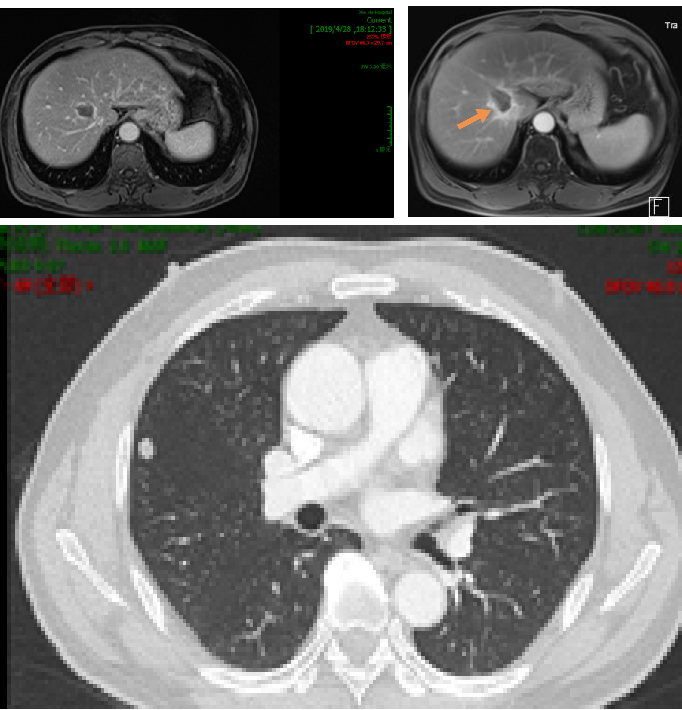

2019年3月胸部CT:右肺上叶近水平裂胸膜处有一枚结节,大小约6mm*5mm,考虑肿瘤转移;腹部MRI:肝右叶S8段新发结节,弥散受限,约16mm*12mm,考虑转移瘤可能性大。

2019.4.10于介入科行肝S8段转移瘤射频消融术。

因肝脏转移瘤靠近血管,射频消融术后复查CT认为肿瘤边缘存在强化,2019.5.27 行肝S8段转移瘤放疗,DT 40GY/5F。

2020.5.28 复查示肝脏及脑干病灶稳定,肺部结节略增大。

3. 肝右叶S8段异常强化灶,考虑转移性肿瘤,较前相仿;